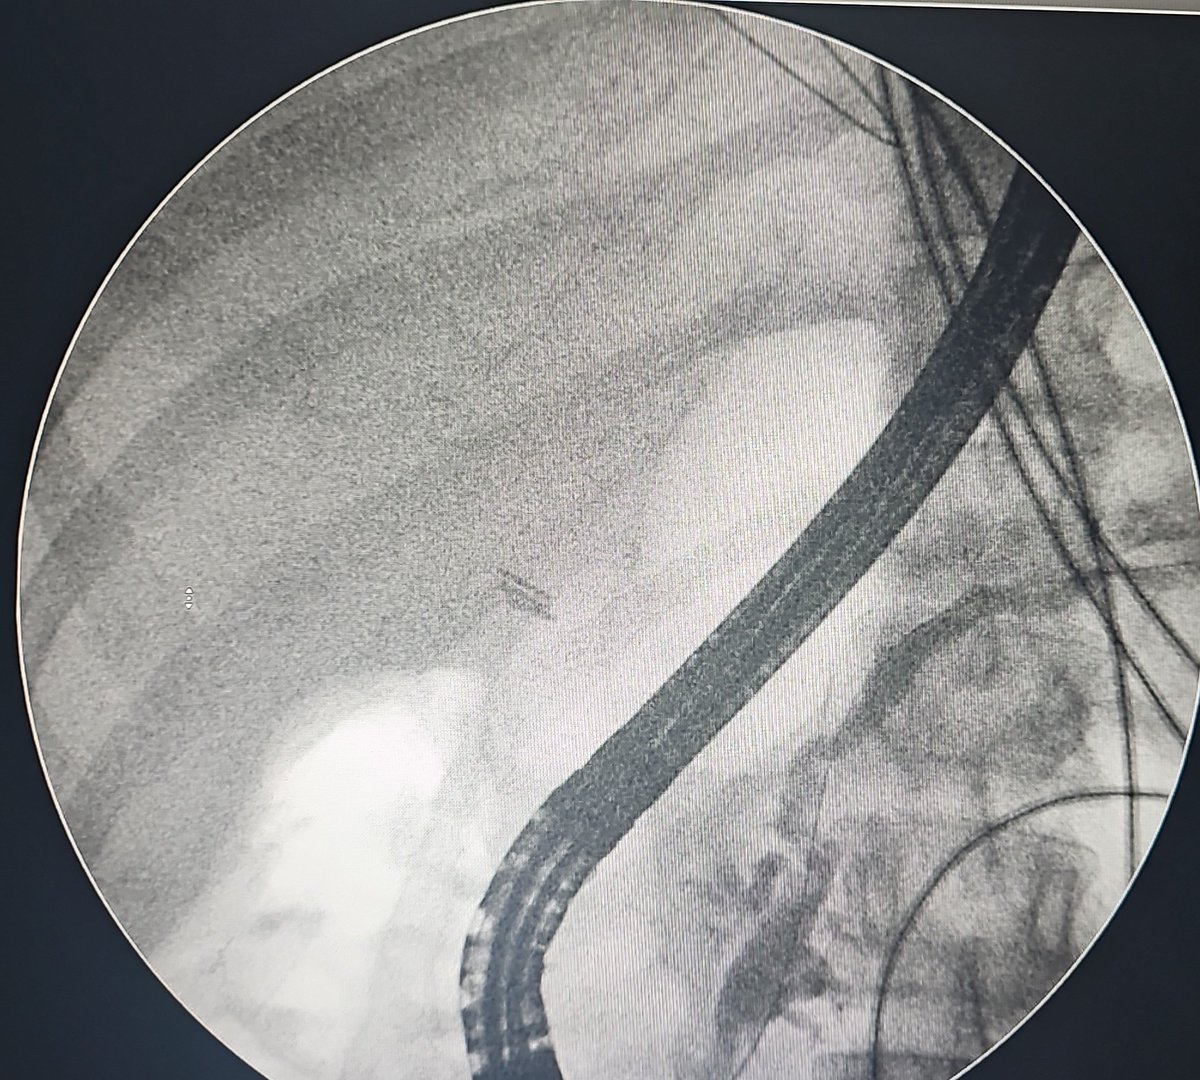

🙍♀️30s Lap CCx➡️CBD injury➡️Open repair 2 wks on, drain output ~400ml/d Pt toxic #ERCP 👉Wire keeps going into collection, cannot negotiate into intrahepatic ducts 👉Contrast - same ??CBD ligated #EUS RZV🙅♂️: Periph ducts decompressed+pneumobilia Options #GITwitter #Surgery?